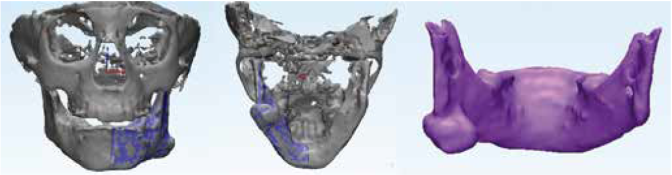

An 8-years-old boy reported to the Department of Oral and Maxillofacial Surgery, Ondokuz Mayis University with a chief complaint of hard swelling in the left posterior region of the mandible. The patient was physically healthy and any systemic condition was not detected during anamnesis. The swelling was not associated with any pain, discharge, fever, paresthesia, or difficulty in mastication. The patient did not recall or confirm any history of trauma or infection in that region. On clinical examination, a solitary, non-pulsatile and approximately 1.5 cm in diameter, bony mass was palpated at the left angle region of the mandible. The tumor found fixed to the underlying bone and the skin overlying the tumor was in a healthy appearance. The panoramic radiography and cone beam computed tomography (CBCT) scan showed a well circumscribed, radiopaque mushroom like image located on the left angle of the mandible (Figure 1, Figure 2). The 3D reconstruction of the computed tomography image revealed a pedunculated homogeneous bony mass attached to the left angle of the mandible (Figure 3). The lesion was completely excised using an extra oral approach under general anesthesia (Figure 4). The surgical specimen was submitted for histopathological examination. Histopathological examination revealed a sclerotic lamellar bone nodule with almost no intertrabecular space (Figure 5). These features confirmed the final histopathologic diagnosis to be peripheral osteoma. The post-operative course was uneventful with a satisfactory healing (Figure 6) . The patient is still under follow-up.

Usage of the most effective imaging modality pose a crucial role in the conservative management of the osteomas. Different imaging modalities like occlusal and panoramic radiographs, Waters view, computerized tomography (CT), magnetic resonance imaging (MRI), or CBCT can be used for the radiographic examination of POs 28. It is reported that POs in the craniofacial region are best visualized and localized by means of CT 29,30. In most of the cases in the literature the radiographic examination of the osteoma was performed with CT (14-16,31-33. However, because of it requires less radiation doses and provides higher quality of images than CT scan, we preferred CBCT in the radiographic examination of our case. Also, different from the majority of other published cases of osteoma in the mandibular angle, we used 3D modelling in our case to perform the treatment more precisely. As far as we aware, there was only one published case which use CBCT scan and 3D modelling together for the management of the angle osteoma (13).